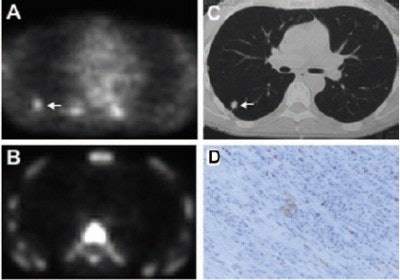

| Images from a patient with history of colorectal cancer and suggestive nodule in right middle lobe, for which histopathology revealed solitary tuberculoma. (A) Transaxial 18FFDG-PET scan demonstrates moderate 18FFDG uptake (arrow) in tumor. (B) No focal tracer accumulation is seen in corresponding 18FFLT-PET scan. (C) Corresponding CT scan shows pulmonary nodule in right middle lobe. (D) On Ki-67 immunohistochemistry, 5% of nuclei show immunoreactivity to Ki-67 antigen. Reprinted by permission of the Society of Nuclear Medicine from: Buck, A., et al. Imaging Proliferation in Lung Tumors with PET: 18FFLT Versus 18FFDG. J Nucl Med 2003, 44:1426-1431. |

In the FDG-PET studies, the mean SUV in the visible lesions was 4.1, and the mean maximum uptake was 6.9. In the 13 patients with NSCLC, the mean SUV was 5.6 and the mean maximum uptake was 9.7. The authors noted that four of the eight patients with benign lesions presented with focal FDG uptake.

For the FLT studies, the researchers reported a mean SUV of 1.8 in all visible lesions, and a mean maximum uptake of 2.7. In the NSCLC patients, FLT SUV was 3.2 and the mean maximum uptake was 4.7. They noted that no benign tumors showed local FLT uptake.

"Increased FLT uptake within a nodule was identified in 11 of the 13 patients with histologically confirmed NSCLC," they wrote.

The authors found a significant correlation between tumoral FLT uptake and proliferative activity as indicated by their Ki-67 immunostaining of malignant tissue specimens, with a mean correlation coefficient of 0.92 for FLT compared with a mean of 0.59 for FDG.